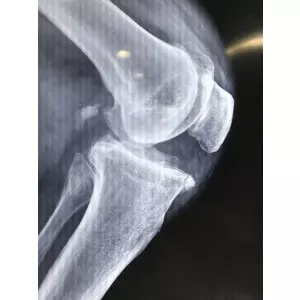

Jay Patel - USA